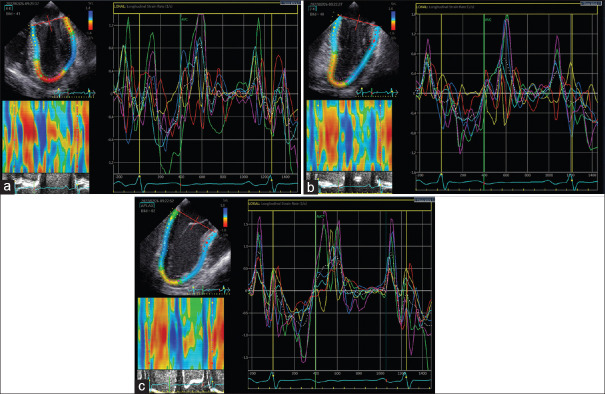

Methods: Prospective observational study including 30 adult patients. Intraoperative transesophageal echocardiography (TEE) was performed after induction of anesthesia [T1], after termination of cardiopulmonary bypass [T2], and after sternal closure [T3]. TEE assessment included the evaluation of peak longitudinal strain rate during isovolumetric relaxation (SR-IVR), early (SR-E) and late (SR-A) LV filling, as well as of conventional echocardiographic measurements and LVDD grading algorithms.

Results: Diastolic strain analysis was feasible in 27 (90%) AVR patients at all time points of assessment. LV diastolic strain improved significantly after AVR [T1 vs T3] as measured by SR-IVR (0.31 s-1 (IQR 0.22; 0.38) vs. 0.4 s-1 (IQR 0.33; 0.43); P = 0.01), SR-E (1.13 s-1 (IQR 0.89;1.28) vs. 1.35 s-1 (IQR 1.10;1.52); P = 0.035), and E/SR-IVR (2.2 m (IQR 1.7;2.8) vs. 1.6 m (IQR 1.3;2.2); P = 0.013). In contrast, conventional echocardiographic measurements and grading algorithms were not able to detect these changes in the same period.

Abstract Image